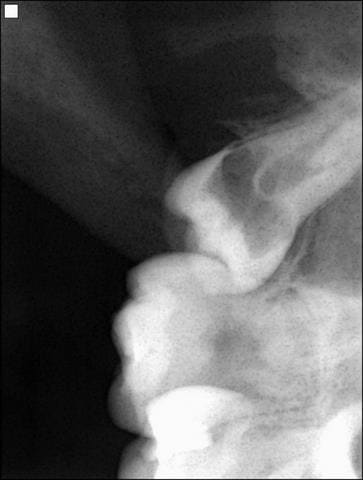

Que pensez vous de cette 18 dont une cuspide apparaît en bouche? Patiente de 18 ans. Que serait votre abord chirurgical face au risque de la projeter dans le sinus, ou comment gérer la couronne cariée

D'après la rx la couronne est palatinée la racine ets donc distalée, lambeau fenêtre osseuse vestib et luxation par élévation.

A priori la difficulté de la dds réside dans son accessiblité et la protection postérieure :

- donc prévoir lambeau avec décharge mésiale, souvent la dds max est difficile à voir de visu, surtout que la tienne est bien enclavée sous la 7.

- longue lame ou ecarteur dautrey pour protéger la region post tubérositaire( eviter les projections )

- l'ostéotomie en general se fait manuellement,selon la qualité tres molle de l'os

- apriori aucun besoin de morceller la dent, l'élever en rotation postérieure, syndesmotome faucille faisant le ' tour de rein de la la dds ) de l'avant vers l'arriere et hop....

Bref un cas d'école de la dds maxillaire si les bonnes précautions sont prises.. Mais rapidement délicat si elle s'accroche.